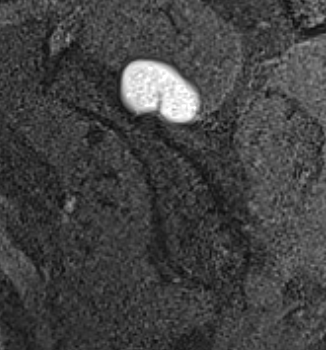

MRI

Spinoglenoid cyst

Spinoglenoid cyst with SLAP tear and posterosuperior labral tear